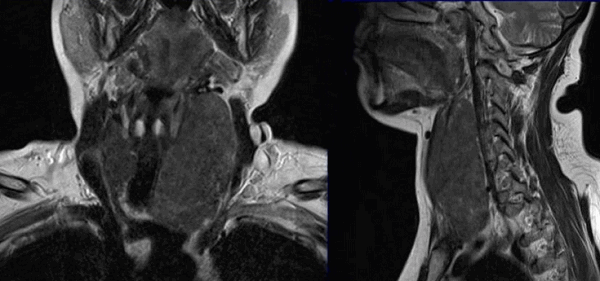

Онкологический процесс на томограммах щитовидной железы

Метод отражает состояние окружающих тканей, позволяет выявить как первичное образование, так и метастазирование опухоли в регионарные лимфатические узлы, загрудинную область, ткани шеи. Точную локализацию очага и степень прорастания атипичных клеток в соседние структуры устанавливают при помощи трехмерного изображения сканируемой зоны.

Метастазы на снимках МРТ шеи